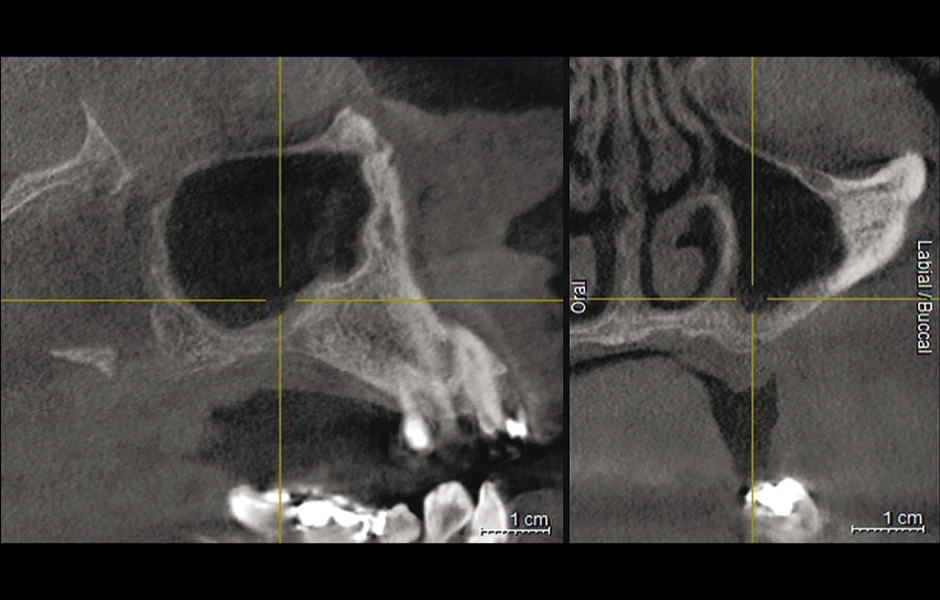

Obr. 11: Dva měsíce po výkonu, na CBCT snímku je vidět volný sinus s širokým přirozeným ústím.

Obr. 3: Po vyjmutí kostěné lamely byla patrná zelenošedá masa; histologie potvrdila aspergilom.

Do studie bylo zařazeno 10 pacientů s aspergilózou maxilárního sinu. U všech pacientů byl na panoramatických snímcích i na CBCT patrný radiopakní stín. CBCT navíc ukázalo, že čelistní dutina byla kompletně vyplněna homogenní patologickou masou. Chirurgická léčba sinu byla provedena za antibiotické profylaxe (Amoxicillin 2 g/den po dobu 7 dní) a intravenózní sedace (Midazolam). Kostní okénko bylo vytvořeno mikropilkou (DENTSPLY Implants), umožnilo bezpečný přístup do sinu. Po odklopení separovaného kostního fragmentu byla aspergilóza spolu s cizorodým materiálem kompletně odstraněna a dutina vypláchnuta peroxidem vodíku (H₂O₂ 3 %). Pro dodatečnou dezinfekci byla použita fotodynamická dekontaminace laserem HELBO (HELBO, Bredent Medical GmbH). Na závěr zákroku byla kostěná lamela vrácena zpět jako biologický uzávěr sinu a fixována resorbovatelnými stehy. Histopatologické vyšetření ve všech případech potvrdilo infekci aspergilózou. Po třech měsících, kdy CBCT potvrdilo nepřítomnost sinusové patologie a průchodné ostium, byla provedena augmentace kosti. Kostní bloky byly odebrány z retromolárové oblasti mandibuly a přeneseny ve 3D konfiguraci podle split-bone block techniky v kombinaci se sinus liftem. Sinus byl augmentován autologní kostí a biomateriálem (FRIOS Algipore®, DENTSPLY Implants) vrstvenou technikou. Po dalších třech měsících byly do augmentované oblasti zavedeny implantáty. O další tři měsíce později byly implantáty odhaleny a následně byla zhotovena definitivní protetická náhrada.“